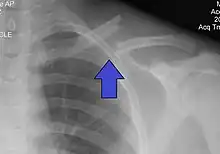

| X-ray of a left clavicle fracture | |